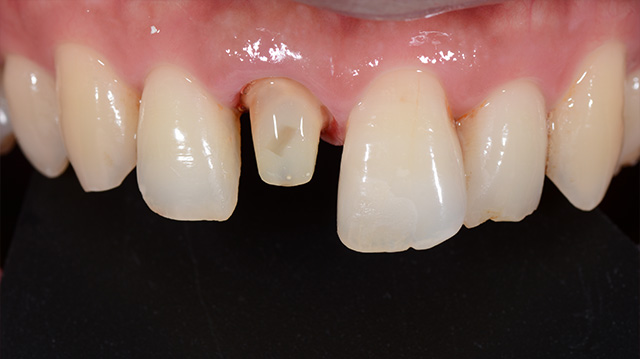

| 年代・性別 | 50代 男性 |

|---|---|

| 主訴 | 転倒して歯が割れた |

| 治療回数 | 3回 |

| 治療期間 | 約1ヶ月 |

| 費用 | 仮歯 5,500円 ジルコニアクラウン 176,000円 |